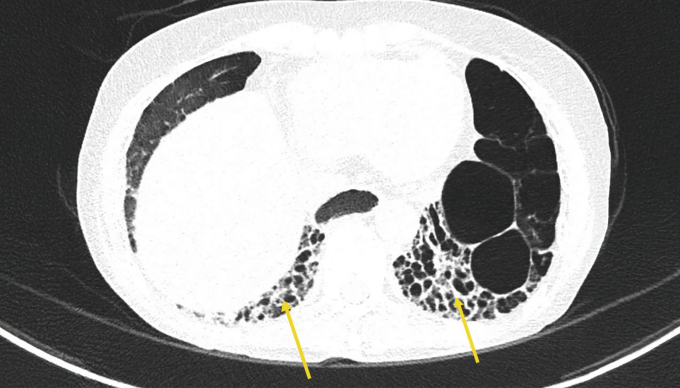

Bác sĩ Tân chỉ định bà Mỹ tầm soát sức khỏe toàn diện. Đây là bước bắt buộc với người mắc xơ cứng bì toàn thể. Kết quả cho thấy bệnh đã âm thầm phá hoại nhiều cơ quan, nghiêm trọng nhất là tăng áp động mạch phổi nặng với mức PAPs:78mmHg, cao gần gấp 3 lần bình thường và tổn thương phổi kẽ khiến giảm trao đổi oxy máu, gây khó thở dai dẳng. Người bệnh cũng bị co thắt mạch máu ngoại biên (Raynaud) mức độ nặng, là nguyên nhân trực tiếp gây hoại tử đầu ngón tay do máu không thể nuôi dưỡng các đầu chi.

Bà nặng 35 kg, thực quản bị giãn đoạn ngực và giảm nhu động - biến chứng điển hình của xơ cứng bì khiến thức ăn khó di chuyển xuống dạ dày, gây triệu chứng nghẹn, ứ đọng và trào ngược axit mạn tính. Theo bác sĩ Tân, đây là lý do bà Mỹ sụt cân và suy kiệt kéo dài. Nếu không được theo dõi và điều trị đúng phác đồ, xơ cứng bì có thể tiến triển tới giảm chức năng phổi nghiêm trọng do tổn thương phổi kẽ và suy tim phải thứ phát do tăng áp động mạch phổi.

Trong một năm điều trị, tình trạng của bà Mỹ không ít lần diễn biến xấu, các đợt ho khan tăng lên khiến nguy cơ xơ hóa phổi kẽ tiến triển, hay các cơn Raynaud bùng phát làm tăng nguy cơ loét và hoại tử đầu chi. Mỗi lần xuất hiện biến chứng, bệnh nhân nhập viện để bác sĩ đánh giá lại chức năng hô hấp, tuần hoàn ngoại biên và điều chỉnh phác đồ điều trị dựa trên mức độ tổn thương phổi kẽ, mức độ tăng áp động mạch phổi, nguy cơ hoại tử đầu chi.